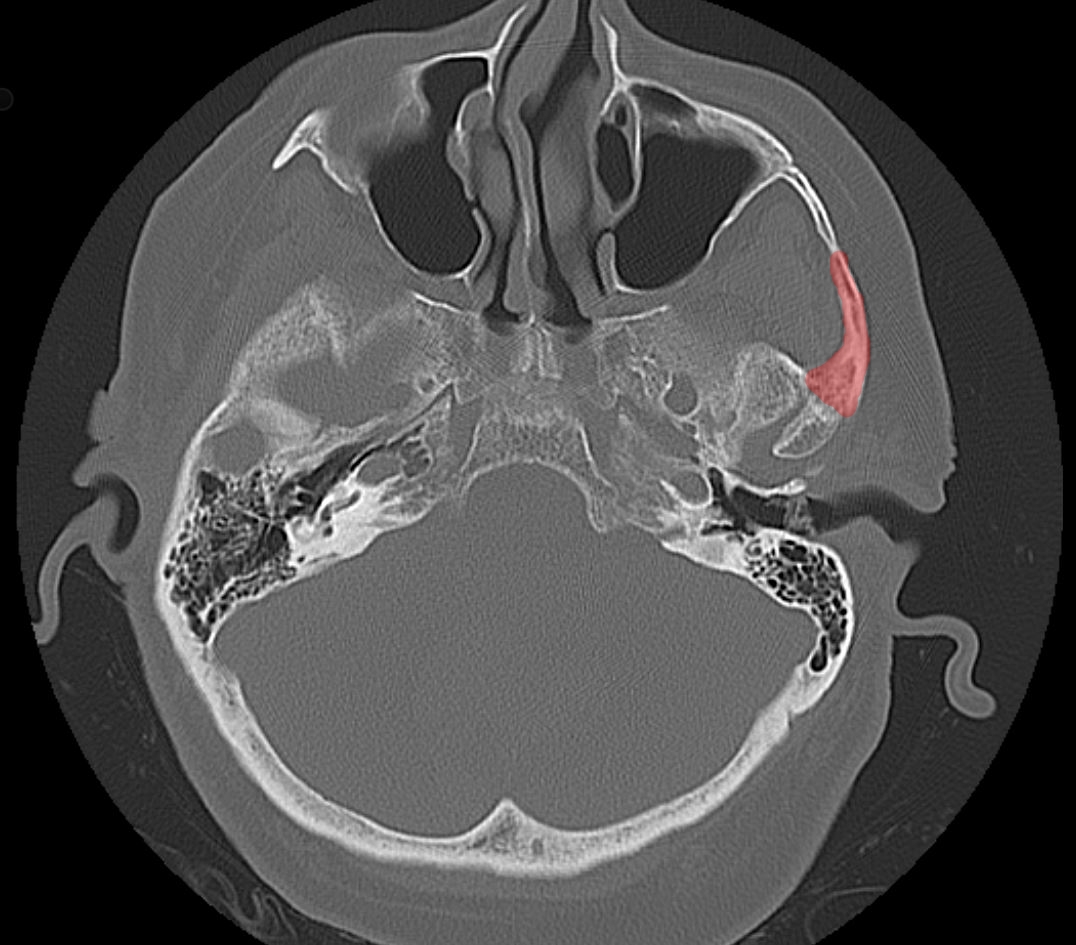

Darstellung des Zygomas in einer axialen CT Bildgebung im Knochenfenster.